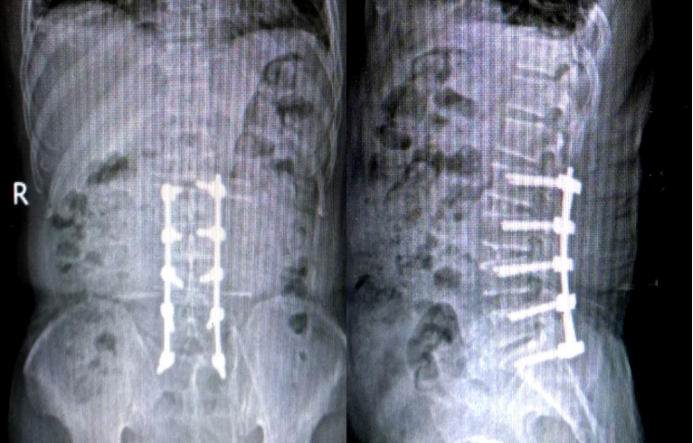

Postoperative 6-month Imaging

6-Month Postoperative Follow-up:

· Implant position: No significant change compared to the immediate postoperative position.

· Dynamic Radiographs:

o Hyperextension position: 42.9°

o Hyperflexion position: 42°

o Intervertebral angle difference: 0.9°

o Intervertebral translation distance: 0 mm

· Implant Status: No deformation, migration, loosening, or fracture observed.

· CT Findings: Indicates fusion status achieved.

· Local Tissue Response: Grade 0.

· Patient Outcomes: Both the Lumbar Function Score and Quality of Life Score showed improvement compared to preoperative levels.